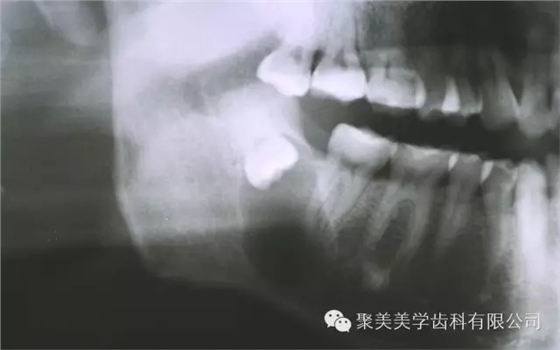

阻生牙不拔,形成囊腫!

放大看!